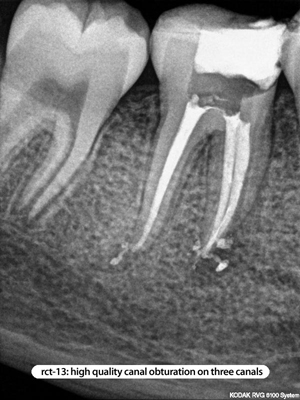

Root Canal Cases